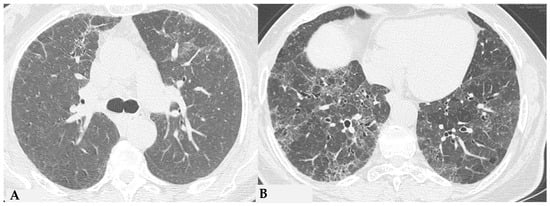

The fibrotic damage in HP is often more severe and extensive in the middle or middle-lower lung zones, but at times, it can be equally distributed across all three lung zones with relative sparing of the subpleural compartment, presenting a “patchy” distribution as a trace of a previous inhalation-mediated immune attack. This distribution may not always exhibit a clear central or peripheral predominance, as evident in axial assessments or MPR reconstructions [7,8,9]. The obstruction of small airways, another significant and distinctive feature of HP, can manifest with various characteristics. In (NFHP), poorly defined centrilobular nodules (fluffy nodules) and mosaic attenuation can be observed. The corresponding HRCT semiotics in FHP presents a “three-density pattern” (Figure 5), characterized by the simultaneous presence of pulmonary lobules with normal density, lobules with (GGO) and lobules with reduced density and size of vascular structures (mosaic attenuation/air trapping) due to air entrapment resulting from broncho-obstruction (Figure 6). The three-density pattern becomes more evident in expiratory HRCT scans due to the air entrapment resulting from the pathogenesis of bronchiole obstruction [4,10].

Figure 5.

FHP: chest HRCT ((A,B): axial scan). Visible is the “three density pattern”, with areas of the lung with normal density spared from pathological changes (red box); areas of the lung with reduced density characterized by a paucity of vascular and bronchial structures (yellow box); areas of the lung with increased density showing reticulations, interstitial thickening and traction bronchiectasis (green box). Lung cyst (red arrow) and areas of smoking-related paraseptal emphysema and advanced destructive emphysema (ADE) (blue arrows) are also present.